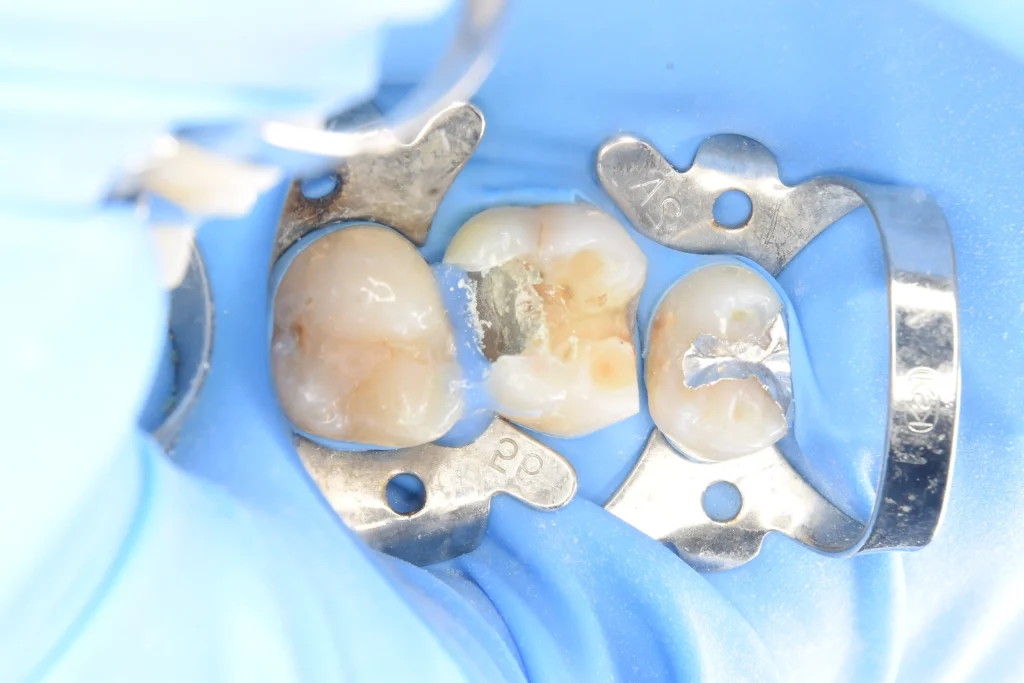

露出面を消毒、神経のあった場所にMTAを丁寧に貼付していきます。

MTAを貼付

神経刺激性の少ない樹脂にてコーティングをしたところです。このまま1ヶ月経過をみて、痛みがなければかぶせものの治療に移行していきます。(その後痛みなく被せ物まで無事に行うことができております。)